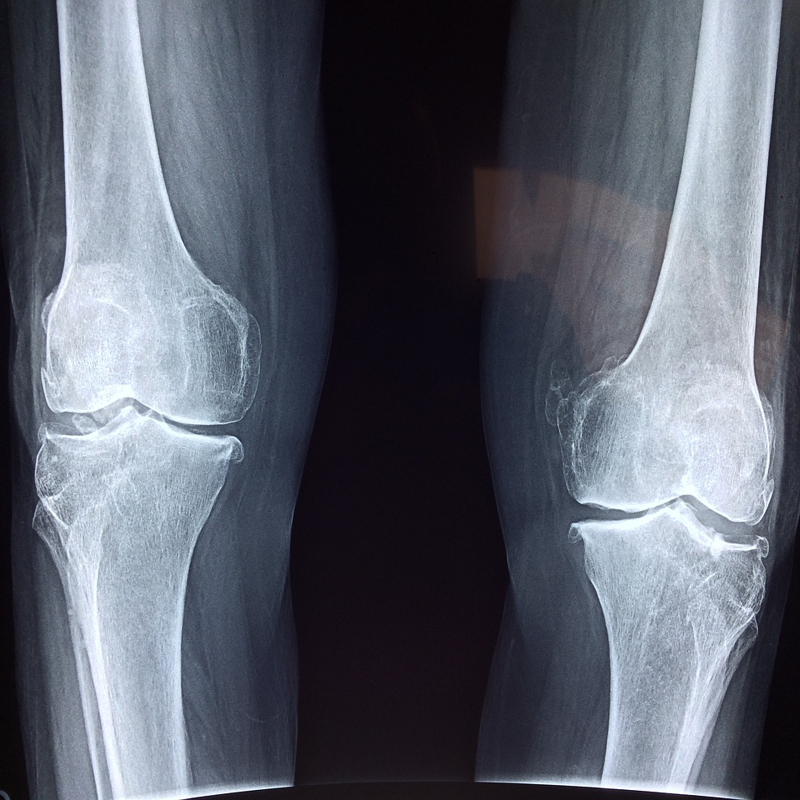

관절염의 원인은 다양합니다. 퇴행성 변화, 염증, 자가면역 질환 등 여러 요인이 복합적으로 작용합니다. 특히 퇴행성 관절염은 나이가 들면서 관절 연골이 닳아 없어지면서 발생하는데, 이는 노화 과정의 일부이지만, 잘못된 생활 습관이나 과도한 체중 부담 등으로 인해 더욱 악화될 수 있습니다. 젊은 층에서도 잦은 운동 부상이나 사고로 인해 관절염이 발생할 수 있으며, 류마티스 관절염과 같은 자가면역 질환은 면역 체계에 이상이 생겨 관절에 염증이 발생하는 질환입니다.

관절염은 뼈와 관절을 둘러싼 연골이 손상되면서 염증과 통증이 발생하는 질환입니다. 우리나라에서도 많은 사람들이 겪고 있는 질환 중 하나이며, 특히 나이가 들수록 발병률이 높아지는 추세입니다. 관절염은 일상생활에 큰 불편함을 초래하며, 움직임이 제한되면서 삶의 질 저하를 가져올 수 있습니다. 매일 아침 일어날 때 뻣뻣한 관절 때문에 움직이기 힘들거나, 계단을 오르내리기 어려울 때, 심지어는 옷 입기조차 힘들어질 때, 관절염의 고통은 삶의 활력을 떨어뜨리고 좌절감까지 느끼게 할 수 있습니다.